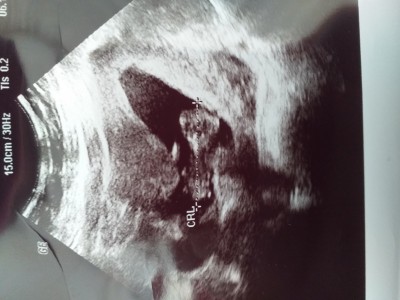

Intrntte bu haftanin goruntulerine baktim ve cevrmdekilere kafalari yuvarlak benimkinin 3 gen gibi neden böyle sorun olurmu

Demedi ama ne bileyim ablamin ayni haftada ultrason gorunrulerine baktim cok duzgun duruyor kafasi

Ablamin bu haftanin aynisinda ultrason goruntlerine baktim cok duzgun duruyor korktm

Ultrason makinesinin kalitesiyle alakalı bi durum canım bu. Bazı makineler var bebeğin her şeyi belli oluyo bazılarında karaltı oluyo